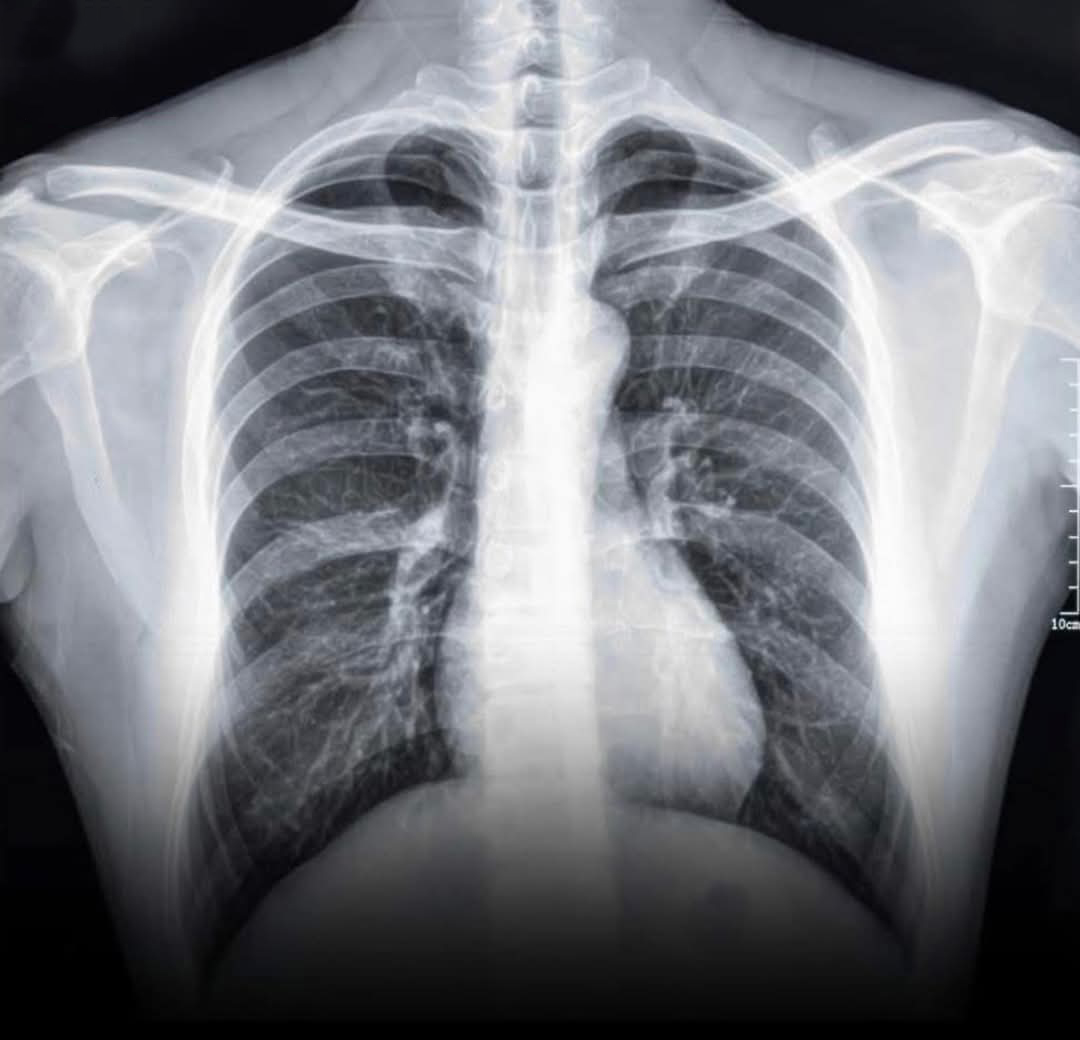

وجّهت طبيبة أردنية تحذيرًا شديد اللهجة إلى الأهالي والمراهقين من مخاطر استخدام أجهزة التدخين الإلكتروني "Vape"، وذلك بعد أن نشرت صورة صادمة تُظهر رئة متليّفة لشاب يبلغ من العمر 16 عامًا، تعرّض لمضاعفات خطيرة بعد عام واحد فقط من استخدام هذه الأجهزة بشكل سري.

وقالت الطبيبة في منشورها: "هاي صورة رئة شاب عمره 16 سنة، كان يستخدم الـVape من ورا أهله.. سنة وحدة بس، كانت كافية تتسبّب بتليّف دائم في الرئة. اليوم، عايش على الأوكسجين ليل نهار، بياخد الاسطوانة معاه على المدرسة، وممنوع يلعب رياضة أو يعيش حياته طبيعي."

وأشارت إلى أن الحالة الطبية التي أصيب بها المراهق تُعرف علميًا باسم "Popcorn Lung" أو Bronchiolitis Obliterans، وهي حالة مرضية نادرة ولكنها خطيرة، تُسبب تلفًا دائمًا في الشعب الهوائية الدقيقة داخل الرئة، ولا يوجد لها علاج يعيد الرئة إلى حالتها الطبيعية.